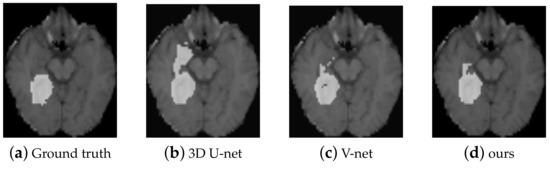

| Method | Depth | Params | Dice Score |

|---|---|---|---|

| 3D U-net | 19 | 23.5M | 0.8554 |

| 3D U-net (Dropout) | 19 | 23.5 M | 0.8592 |

| 3D U-net (s2-conv) | 23 | 25.9 M | 0.8593 |

| [39] | 23 | 25.9 M | 0.8655 |

| V-net [38] | 19 | 23.5 M | 0.8685 |

| 3D U-net (3D-DSC) | 28 | 17.8 M | 0.8932 |